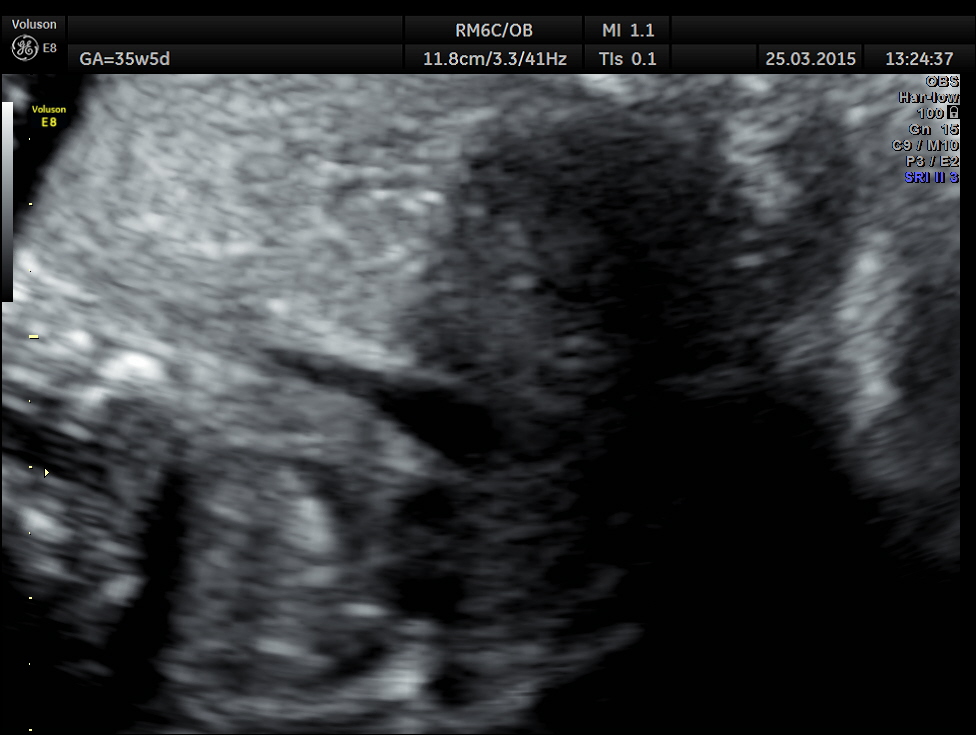

In the three vessel view , single big vessel is seen in a plane.

3 vessel view shows only a single vessel in a given plane.

3 Vessel trachea view show only one great vessel in a given plane.